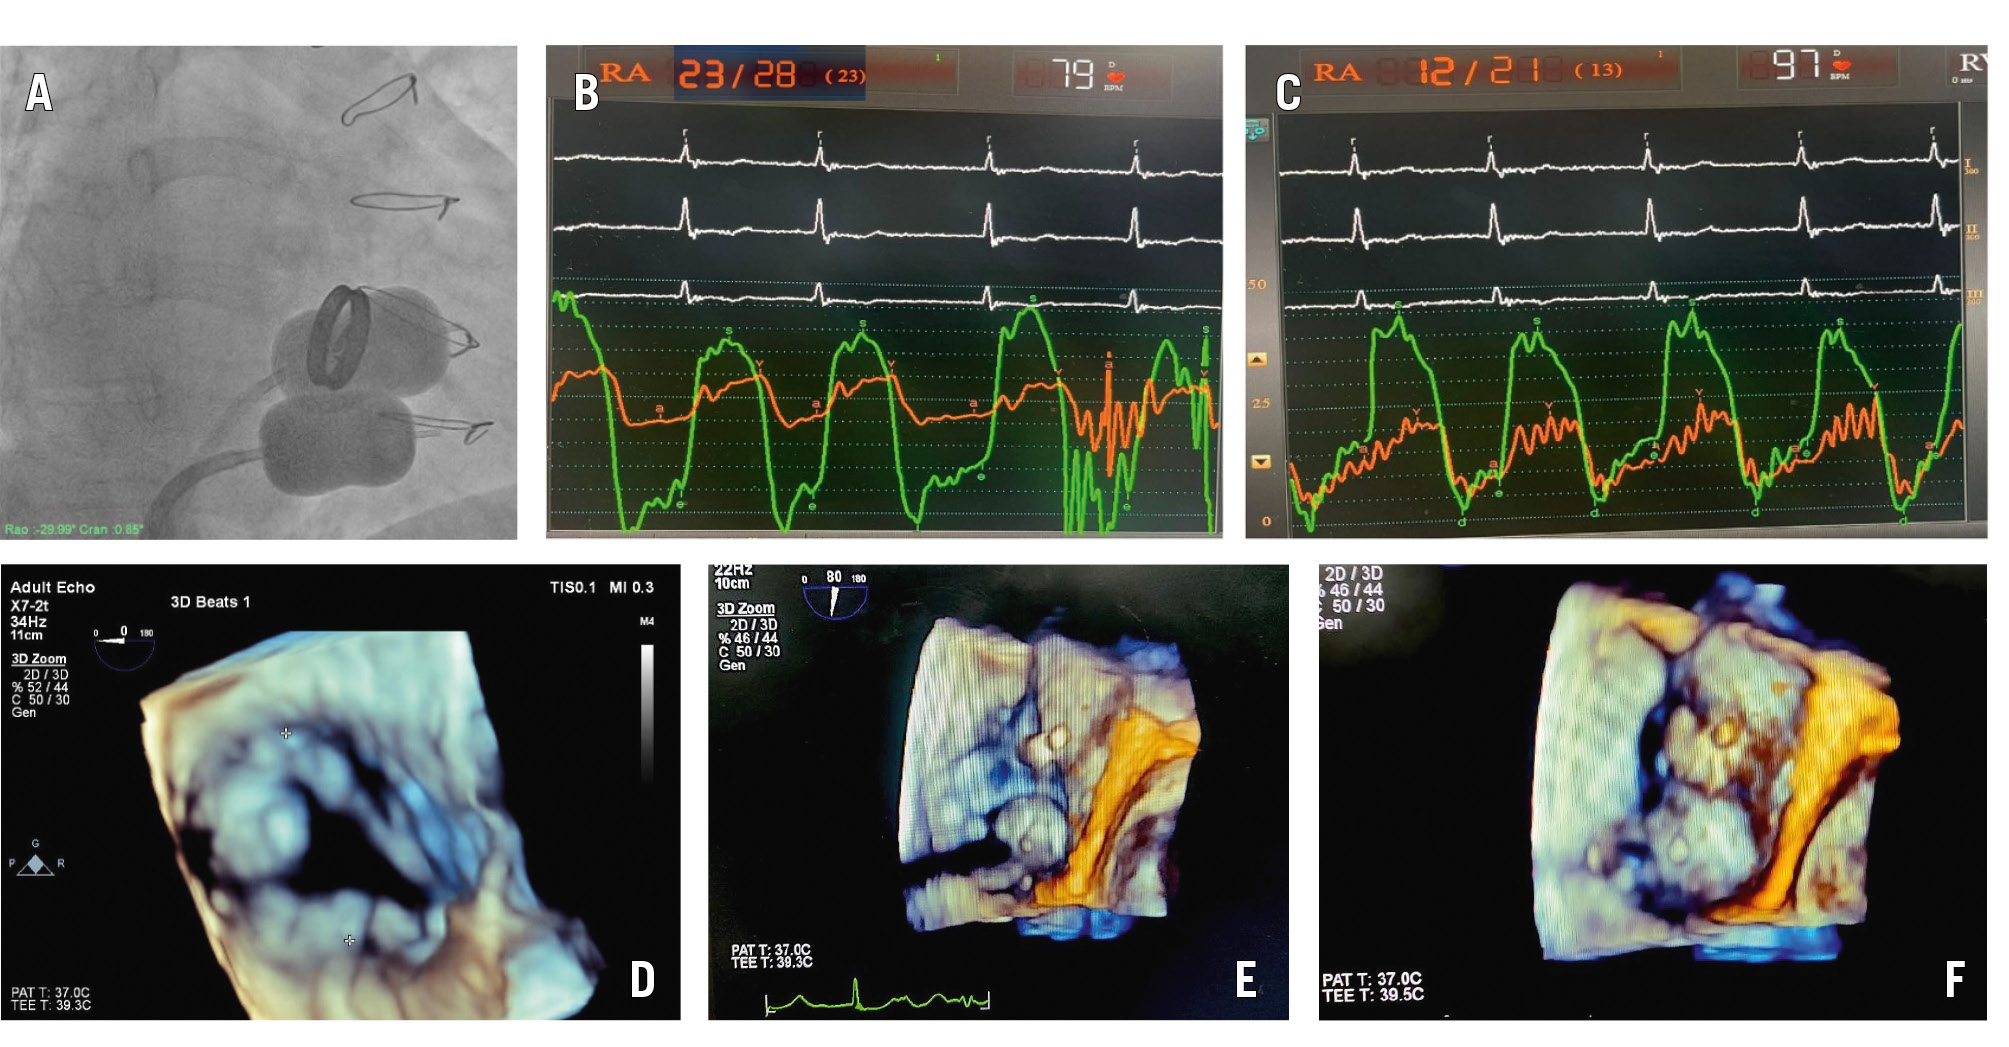

Both right and left femoral venous access were obtained. Two balloons (Accura Balloon Catheter PTMC Balloon [Vascular Concepts]) were introduced via the femoral veins across the tricuspid valve into the right ventricle. Due care was taken to ensure the positioning of the balloons across the tricuspid orifice. This was ensured by inflating and withdrawing the larger balloon first until some resistance was felt. The indentation at the waist marked the plane of the annulus. Once the first balloon was hinged at the annulus, the second balloon was inflated and retracted to the level of the annulus. Once both balloons were positioned at the annulus, they were simultaneously inflated until the waists disappeared (Figure 1A). This required excellent coordination between the two operators (Moving image 1). The haemodynamic parameters and details of the preprocedure and post-procedure echocardiography are summarised in Supplementary Table 1. The pre- and post-procedure haemodynamic tracings from the first patient are shown in Figure 1B and Figure 1C, respectively. No worsening of TR was noted. In the second patient, intraoperative transoesophageal echocardiographic images of the native tricuspid valve and the inflated balloons across the tricuspid annulus were obtained, as shown in Figure 1D–Figure 1E–Figure 1F. At 1-year follow-up, no restenosis was noted, but there was severe TR. However, both patients were asymptomatic at 1 year post-procedure. These findings are summarised in Supplementary Table 2.

Figure 1. Fluoroscopic image, haemodynamic tracings, and 3D transesophageal echocardiographic images of double-balloon tricuspid valvotomy. A-C) First patient: (A) fluoroscopic image of 2 inflated Accura balloons across the tricuspid valve; (B) preprocedure haemodynamic tracing with TVG of 18 mmHg and (C) post-procedure tracings showing no gradient. (D-F) Second patient’s 3D transoesophageal echocardiographic images: (D) native tricuspid valve; (E, F) partially and fully inflated Accura balloons across the tricuspid valve. 3D: three-dimensional; TVG: tricuspid valve gradient